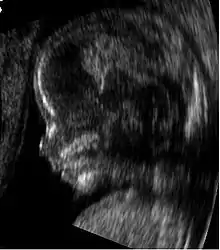

Medical ultrasound is an ultrasound-based diagnostic medical imaging technique used to visualize muscles, tendons, and many internal organs to capture their size, structure and any pathological lesions with real time tomographic images. Ultrasound has been used by radiologists and sonographers to image the human body for at least 50 years and has become a widely used diagnostic tool. The technology is relatively inexpensive and portable, especially when compared with other techniques, such as magnetic resonance imaging (MRI) and computed tomography (CT). Ultrasound is also used to visualize fetuses during routine and emergency prenatal care. Such diagnostic applications used during pregnancy are referred to as obstetric sonography. As currently applied in the medical field, properly performed ultrasound poses no known risks to the patient.[25] Sonography does not use ionizing radiation, and the power levels used for imaging are too low to cause adverse heating or pressure effects in tissue.[26][27] Although the long-term effects due to ultrasound exposure at diagnostic intensity are still unknown,[28] currently most doctors feel that the benefits to patients outweigh the risks.[29] The ALARA (As Low As Reasonably Achievable) principle has been advocated for an ultrasound examination – that is, keeping the scanning time and power settings as low as possible but consistent with diagnostic imaging – and that by that principle nonmedical uses, which by definition are not necessary, are actively discouraged.[30]